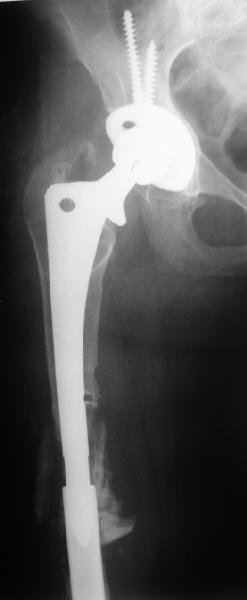

Female, rheumatoid, THA in 2003, car accident in 2006, failed plating. Nailing in Oct 2007. The nail is solid with hollow proximal part where the stem is docked. Last images are in 1 year after

nailing.

I have refreshed respect for the mighty femur and it’s incredible/remarkable ability to unite, regardless of what we do to it.

The femur responded by failure to Mennen plating (DePuy Bridge plate). So i would add that the ability to unite is realized in mechanically and biologically sound conditions.